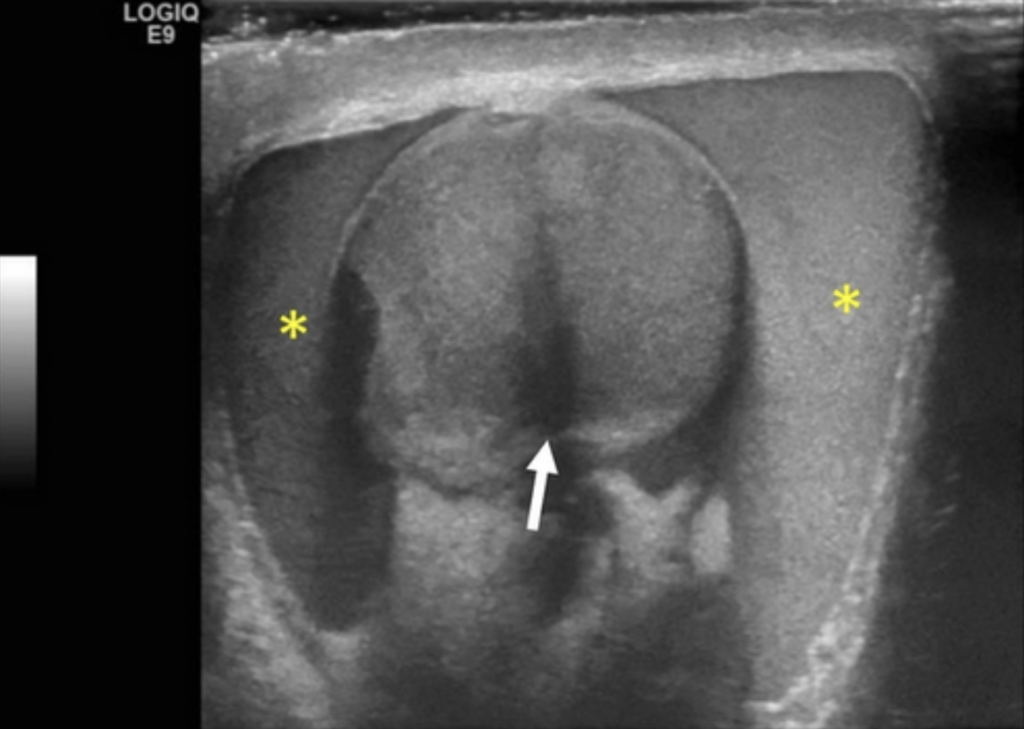

Epididymo-orchitis. Normal right testis (A), with left testis (B) showing epididymis (thick arrow), increased blood flow, and reactive hydrocele (thin arrow). Source: Mandava et al., 2020.

- Findings: In epididymitis, there is typically enlargement of the epididymal head on ultrasound. If there is accompanying orchitis, Doppler will show asymmetrically increased color flow in the affected testis.

- Epididymo-orchitis

- Presentation: Gradual onset of warm, painful, and swollen scrotum, accompanied by urinary symptoms.